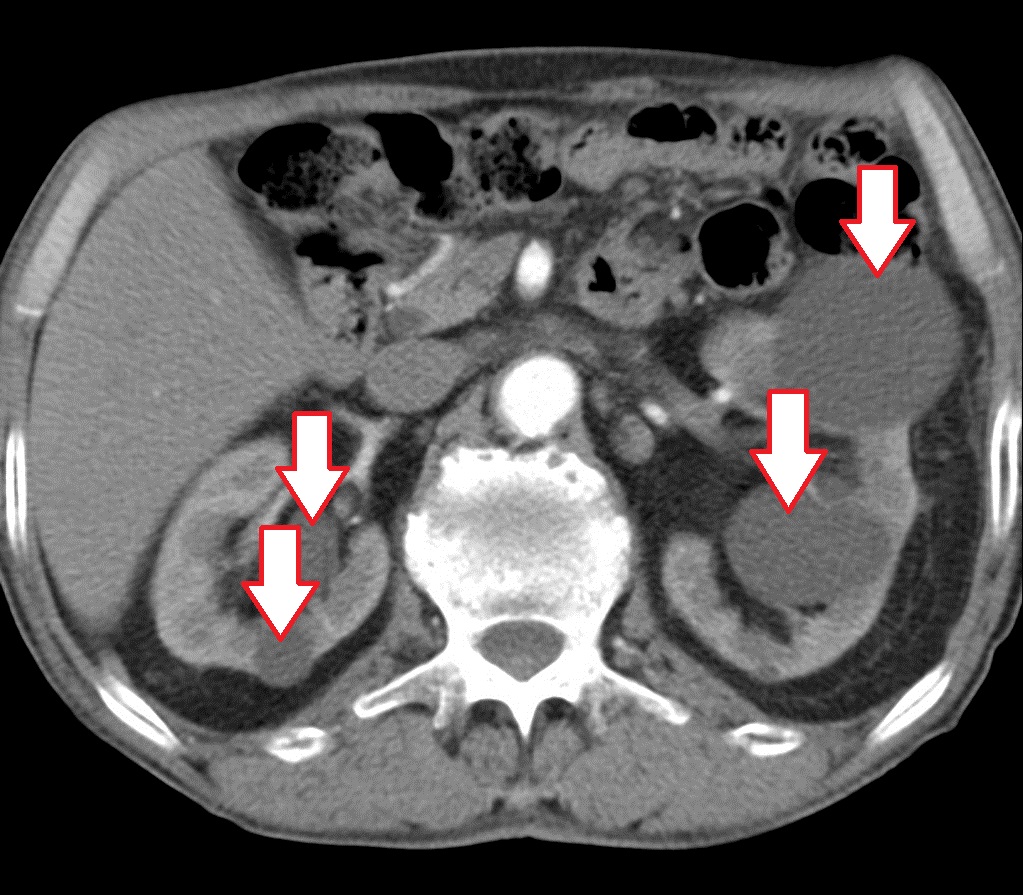

Методы динамического контрастирования печени на МРТ

Раздел: Снимки-подсказки